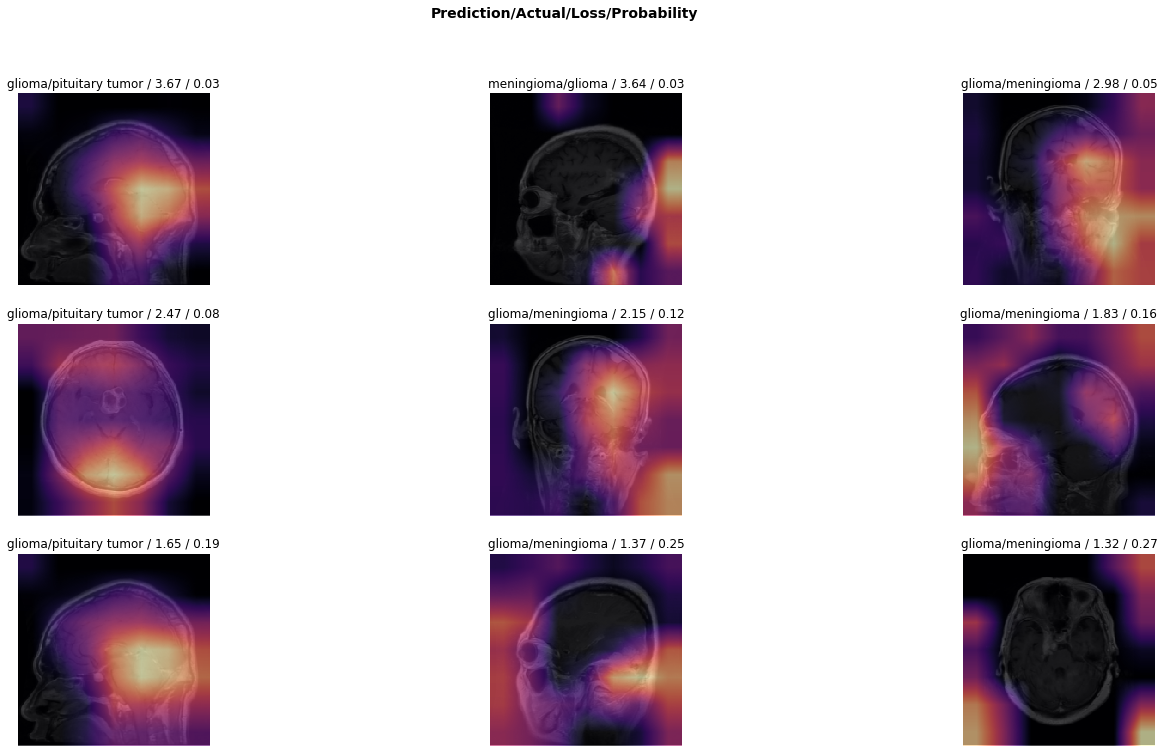

In this third and final experiment, we used the brain MRI dataset from the School of Biomedical Engineering, which consists of T-1 weighted images. We re-trained the model as a benchmark. We froze the convolution layers of the network and did not update it during this stage. We only trained the weights of the fully-connected layers of the model. We used the multinomial logistic cost function to measure the loss and error rate with a step size of 1e31superscript𝑒31e^{-3} and trained the model for 4 epochs. We set the number of epochs to 4 to ensure the model does not overfit on the training set. The model memorises the given small dataset which affects out-of-sample performance. On completing the first stage of the training, the model showed an overall accuracy of 96.73% using a fivefold cross-validation strategy. Fig 24 shows the top miss-classified images during this phase of training.

Refer to caption

Figure 24: Illustration of top miss-classified images after stage I of training